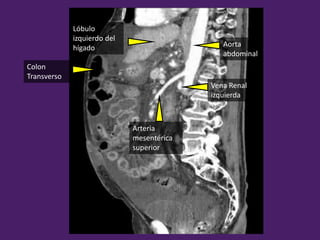

Lóbulo

izquierdo del

hígado

Colon

Transverso

Aorta

abdominal

Arteria

mesentérica

superior

Vena Renal

izquierda